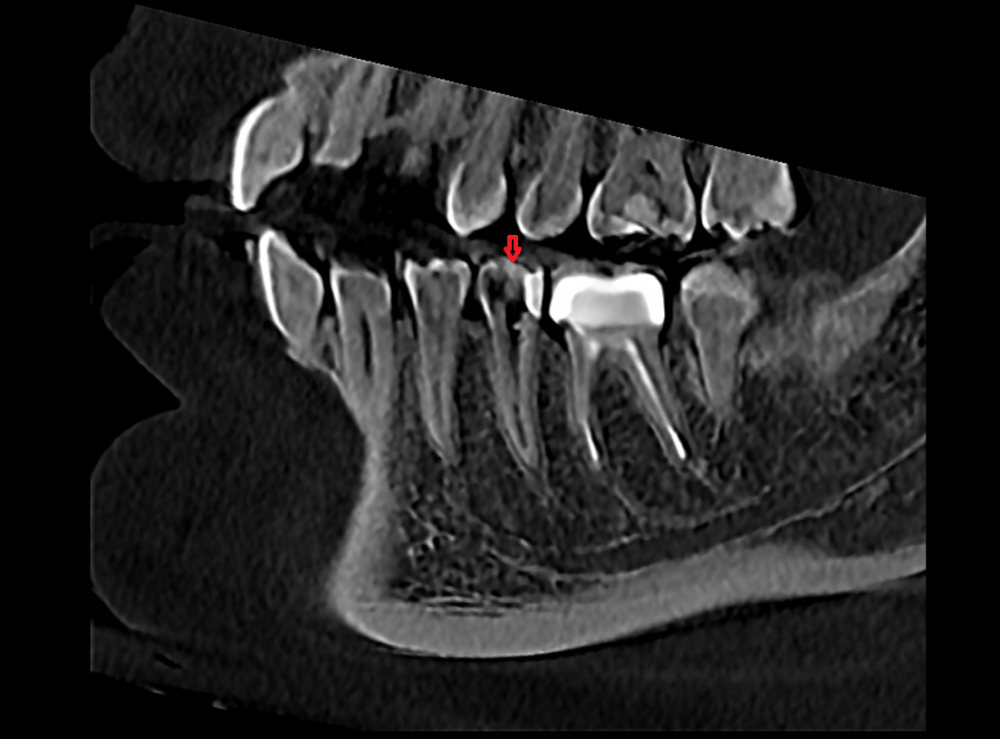

Доброго времени суток, уважаемые форумчане и врачи! Хочу попросить вашего участия в теме, тк ситуация выглядит нестандартной. Дано: 5ый нижний зуб слева, рядом коронка на 6ом.

6. Сделала КТ, врач говорит, что с зубом все ок, нижнечелюстной канал задет быть не может. Сегодня запломбировали постоянным материалом, но симптоматика по жжению, пульсации(при надкусывании) и лёгкому онемению осталась.

На фото - 5ый нижний зуб рядом с жевательной коронкой. Подскажите, пожалуйста, в чём может быть проблема.

Добрый день. До магистрального нерва по кт далеко, его задеть точно не могли. Насколько хорошо запломбировали канал оценить невозможно, т.к.  не приложили снимок после лечения.